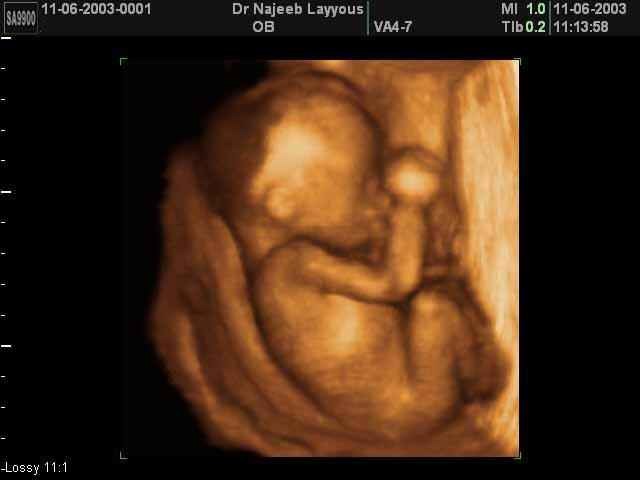

• Month 3

Month 3

about 1 inch long

nostrils mouth lips teeth and eyelids form

fingers and toes almost complete

all organs are present but immature